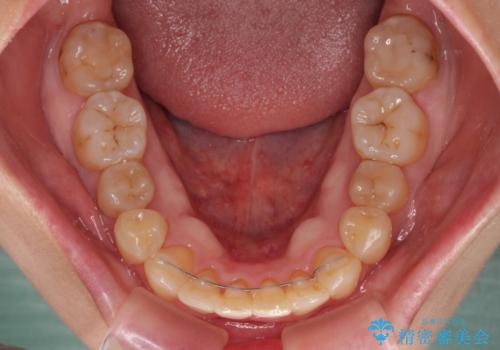

前歯のデコボコをワイヤー矯正できれいに整える

舌の突出癖により治療期間中に開咬となり、治療が長引きましたが、口元も治療前よりも引っ込めることができ、すっきりとした仕上がりとなりました。